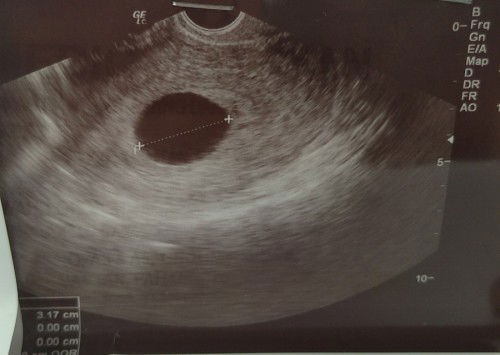

Kalau scan perut x nmpak mungkin normal lagi.. kalau tvs pun x nmpak kemungkinan blighted ovum. Lagi2 kalau period jenis tratur. Ni scan keberapa kali ni? Sbab tengo ukuran kantung pun lebih 3cm dah spatutnya ada baby dah dlam tu

Kemungkinan blighted ovum sis. Sbab dah scan since 6w lagi. Kalau normal setiap 2w dah nmpak perubahan mcm 6w kantung je, 8w nmpak janin and heartbeat, 10w nmpak bentuk baby and tangan kaki smua dah. Lain la kalau sis baru 1st time scan. Lagi2 dah scan ikut bawah kan? Sbab biasanya scan bawah lagi tepat nmpak jelas